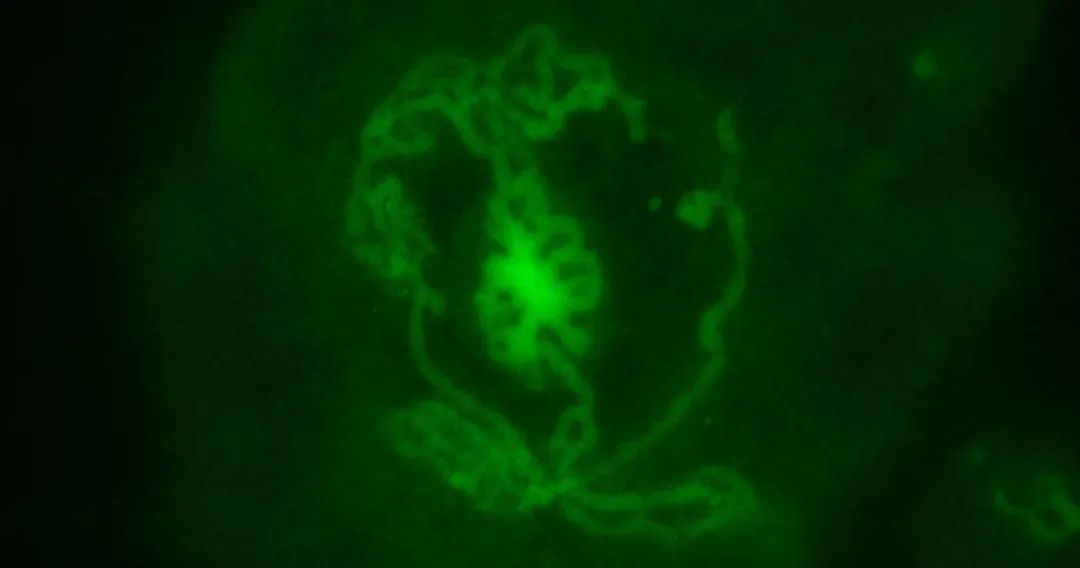

研究团队从新生小鼠中提取了未成熟睾丸细胞用于培养睾丸类器官,其形成了与体内天然睾丸高度相似的管状结构和组织,这表明了睾丸类器官的成功构建,这些管状结构与天然睾丸中存在的多条生精小管相似,这些小管是精子发生的场所。